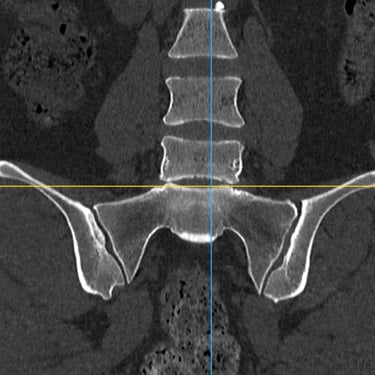

Manejo quirúrgico de la hernia lumbar con inestabilidad: enfoque moderno con FTP y TLIF

La hernia lumbar con inestabilidad vertebral es una patología frecuente que causa dolor lumbar persistente, ciática y limitación funcional, afectando la calidad de vida del paciente. Cuando el tratamiento conservador no logra resultados adecuados, la cirugía se convierte en la mejor opción terapéutica. La fijación transpedicular con tornillos (FTP) junto con la técnica TLIF (Transforaminal Lumbar Interbody Fusion) permite estabilizar la columna, descomprimir las estructuras nerviosas y lograr una adecuada fusión ósea. Este abordaje, especialmente mediante técnicas mínimamente invasivas (MISS), ofrece múltiples beneficios, como menor daño muscular, menor dolor postoperatorio y recuperación más rápida, facilitando el retorno temprano a las actividades cotidianas con mejores resultados clínicos.